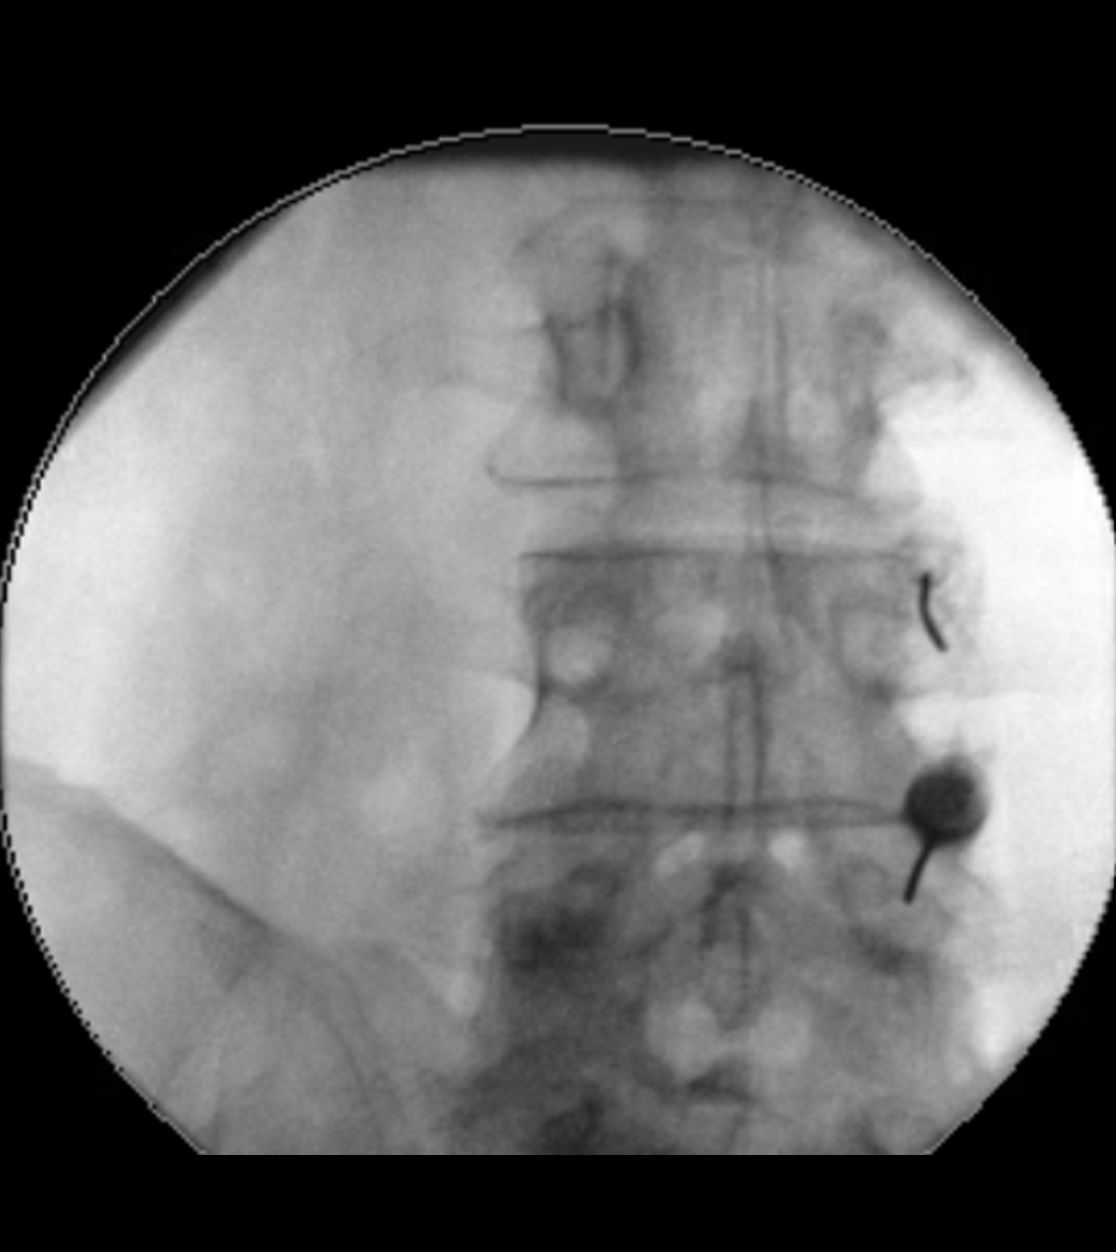

Bei der Rückenmarkstimulation wird in der Wirbelsäule eine Elektrode platziert. Über diese werden elektrische Impulse an das Rückenmark abgegeben. Die Elektrode ist mit einem Impulsgeber (vergleichbar mit einem Herzschrittmacher) verbunden. Das operative Verfahren gliedert sich in zwei Abschnitte: Im ersten Eingriff erfolgt, unter örtlicher Betäubung und Röntgenkontrolle, die Platzierung der Elektrode im Rückenmarkskanal. Im Anschluss erfolgt eine Testphase. Ziel ist es, die Abdeckung des Schmerzareals durch die Stimulation und die daraus resultierende Schmerzreduktion zu testen. Bei zufriedenstellendem Ergebnis wird in einem zweiten Eingriff der Impulsgeber unter die Haut implantiert.

Röntgenbild zur Rückenmarkstimulation

Sollte bei einer Trigeminusneuralgie eine mikrovaskuläre Dekompression nicht infrage kommen, so kann als minimalinvasives Verfahren eine „Verödung“ des Ganglion Gasseri zu einer Schmerzlinderung führen. Hierbei wird unter Röntgenkontrolle eine dünne Nadelelektrode in das Ganglion Gasseri geschoben und mit gezielten Wärmestrahlen eine selektive Vernarbung der Nervenfasern vorgenommen, die für die Schmerzübertragung verantwortlich sind. In einigen Fällen ist im Verlauf bei einer erneuten Zunahme der Beschwerden eine Wiederholung der Prozedur notwendig.

Röntgen-gestützte Infiltrationen stellen eine präzise und schonende Methode zur Behandlung von Rücken- und Gelenkschmerzen dar. Durch den Einsatz von Röntgenbildwandlern wird die genaue Position der Nadel während des Eingriffs sichtbar gemacht, wodurch eine präzise und zielgerichtete Behandlung möglich ist. Zielgebiete der Infiltration sind hierbei die sog. Facettengelenke oder das Ileosakralgelenk (ISG). Wenn die infiltrative Methode nicht ausreicht bzw. die Schmerzlinderung nur kurz anhält, setzen wir auch Facettenthermokoagulationen ein, bei denen durch gezielte Wärmeanwendungen an den betroffenen Nerven die Schmerzübertragung blockiert wird.

Infiltration von Facettengelenken

Infiltration eines Ileosakralgelenks